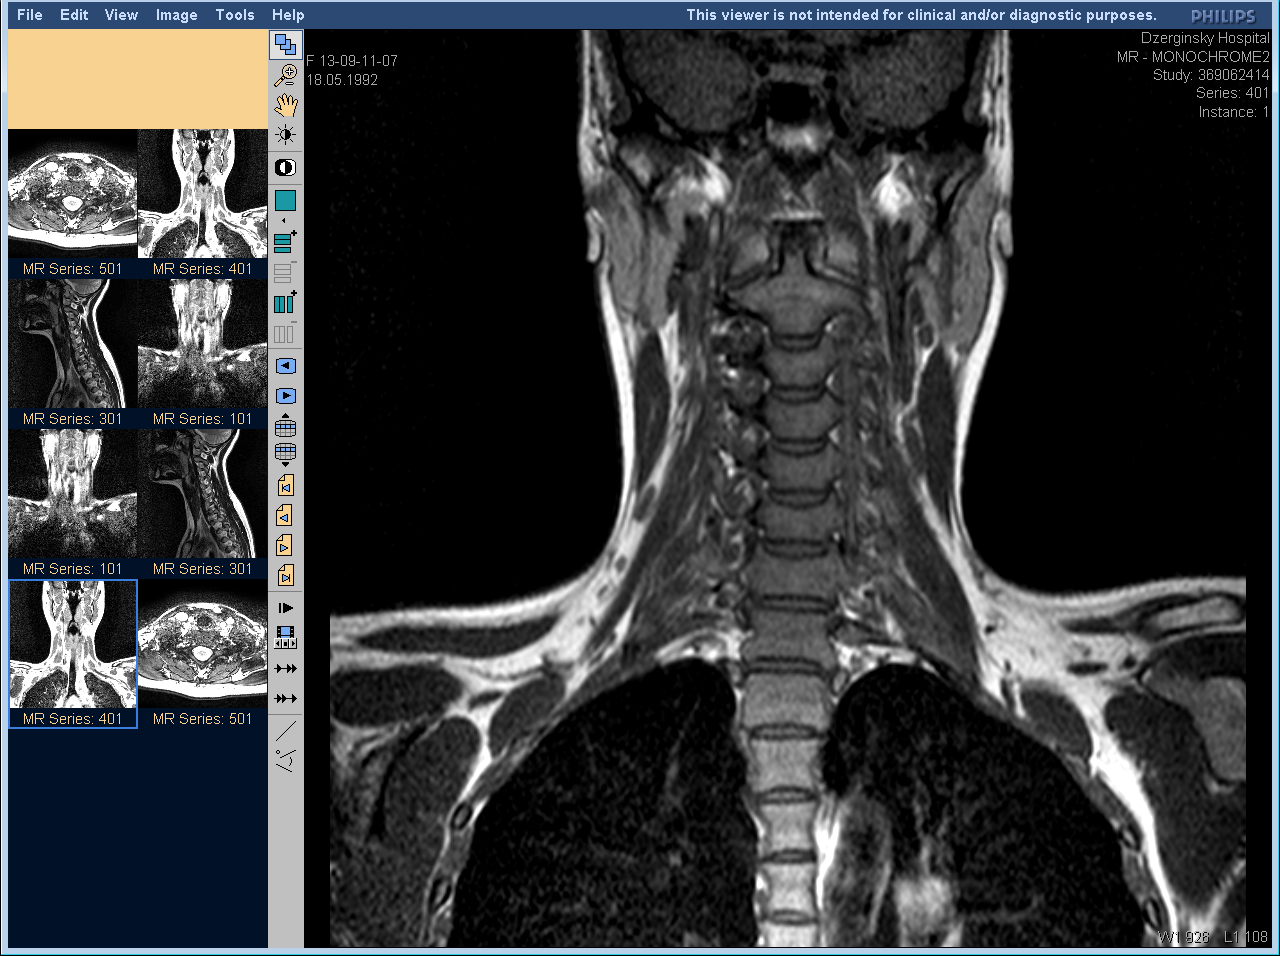

Компьютерная и магнитно-резонансная томография дают более точные результаты, но имеют ряд противопоказаний, поэтому назначаются не всем пациентам.

МРТ шейного отдела позвоночника и сосудов шеи